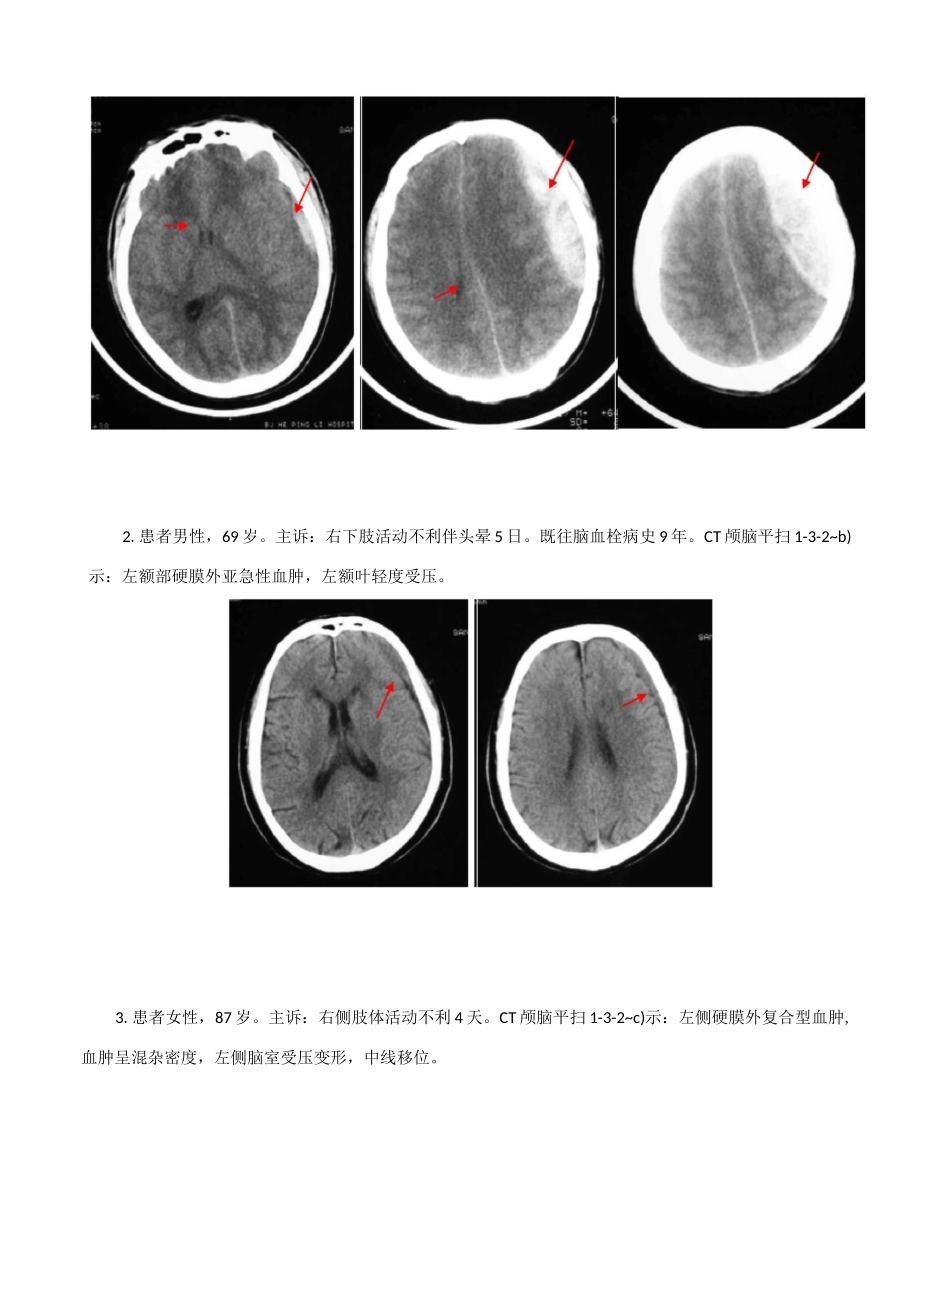

2.患者男性,33 岁。主诉:头部外伤半小时,昏迷。查体:左外耳道及右鼻腔鲜血。CT 颅脑平扫 1-3-1~d)示:左眼眶骨折,硬膜外少量积气,双筛窦及蝶窦内积血。左乳突部骨折及蛛网膜下腔出血。由直接一、颅骨损伤第三节颅脑损伤CT 对颅骨骨折可见到骨碎片及凹陷骨折的深度,同时窦、筛窦等诸窦腔的积血。对开放性骨折可见血肿内、脑胀及血肿也易显示。【病例】膜下腔积气上颌窦、蝶筋膜下的肿1.患者男性,69 岁。主诉:头、胸部外伤 12 天,一过性意识丧失。CT 颅脑平扫 1-3-1~b)示:右额叶皮质少量出血,额骨及左枕骨线性骨折,左枕帽状筋膜下水肿。外力引起骨折,伤及血管,血液聚集于硬膜外腔。由于硬膜与颅骨粘连紧密,表现为颅骨内板下方局限性梭形/半月形高密度,边缘光滑锐利。如为开放性骨折,血肿内可见气体。也可并发脑实质损伤,重者出现脑室变形移位及中线移位。静脉源性硬膜外血肿,因静脉压力低,血肿形成缓慢。CT 扫描时,血肿可能溶解,表现为高密度或低密度区。若横跨半球且压迫大脑镰向下的硬膜外血肿,常见于静脉窦撕裂。少数病例受伤时并无症状,后发现慢性硬膜外血肿,CT 平扫呈等密度,增强扫描可显示血肿内缘包膜强化,有助于等密度硬膜外血肿的诊断。【病例】1.患者男性,35 岁。主诉:从 4 米高跌下后头部受伤伴头晕。CT 颅脑平扫 132~c)示:左额顶区硬膜外血肿,脑室变小,脑肿胀,并蛛网膜下腔出血。最终死亡。由直接132.患者男性,69 岁。主诉:右下肢活动不利伴头晕 5 日。既往脑血栓病史 9 年。CT 颅脑平扫 1-3-2~b)示:左额部硬膜外亚急性血肿,左额叶轻度受压。3.患者女性,87 岁。主诉:右侧肢体活动不利 4 天。CT 颅脑平扫 1-3-2~c)示:左侧硬膜外复合型血肿,血肿呈混杂密度,左侧脑室受压变形,中线移位。1.患者男性,74 岁。主诉:脑外伤后 1 天,昏迷。CT 颅脑平扫 1-3-3~c)示:右额叶局限性血肿,左顶三、硬膜下血肿发生在硬脑膜与蛛网膜之间的血肿。由于蛛网膜无张力,与硬脑膜连接很薄弱,故血肿范围较广。形状大多呈新月状,可超过颅缝,甚至可占据整个大脑半球的硬脑膜下腔。可分急性、亚急性、慢性,以亚急性多见。急性时间在 3 天以内。CT 表现为高密度,个别也可为混杂密度、等密度甚至低密度(系蛛网膜破裂,脑脊液进入血肿所致,或患者严重贫血)。亚急性时间为 4 天至 3 周,系急性向慢性发展的过渡阶段。CT 表现的形态及密度均多样化。形态可有新月形...